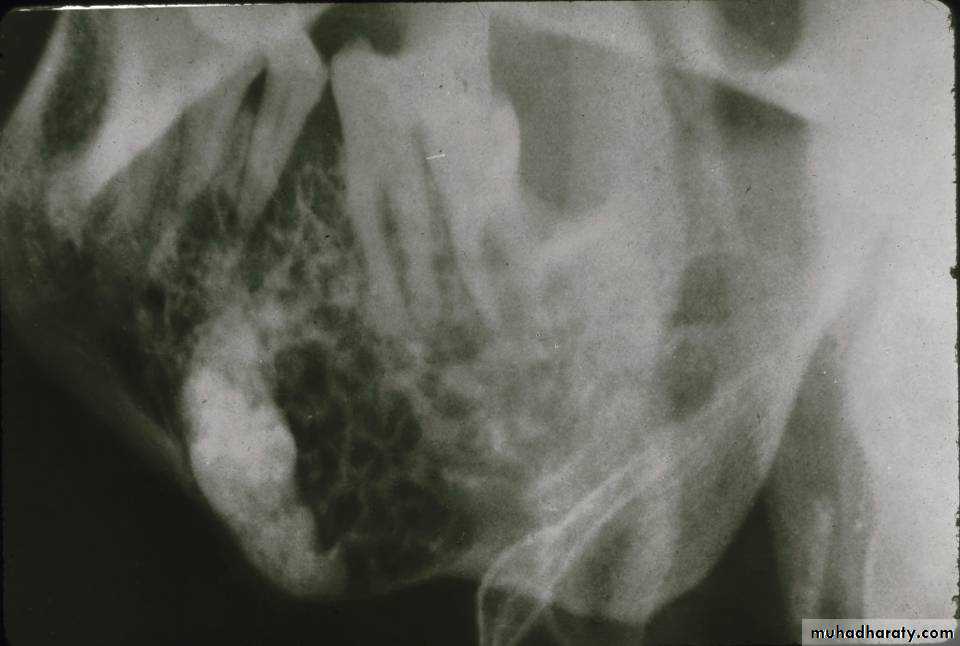

• Early lesions are radiolucent with smooth, well-defined contours.

• Later a well-defined radiopaque appearance develops.• The compound type shows apparent tooth shapes while the complex type appears as a uniform opaque mass with no apparent tooth shapes present.

Odontoma

Radiographical features